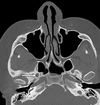

cribiform plate of ethmoid bone

13